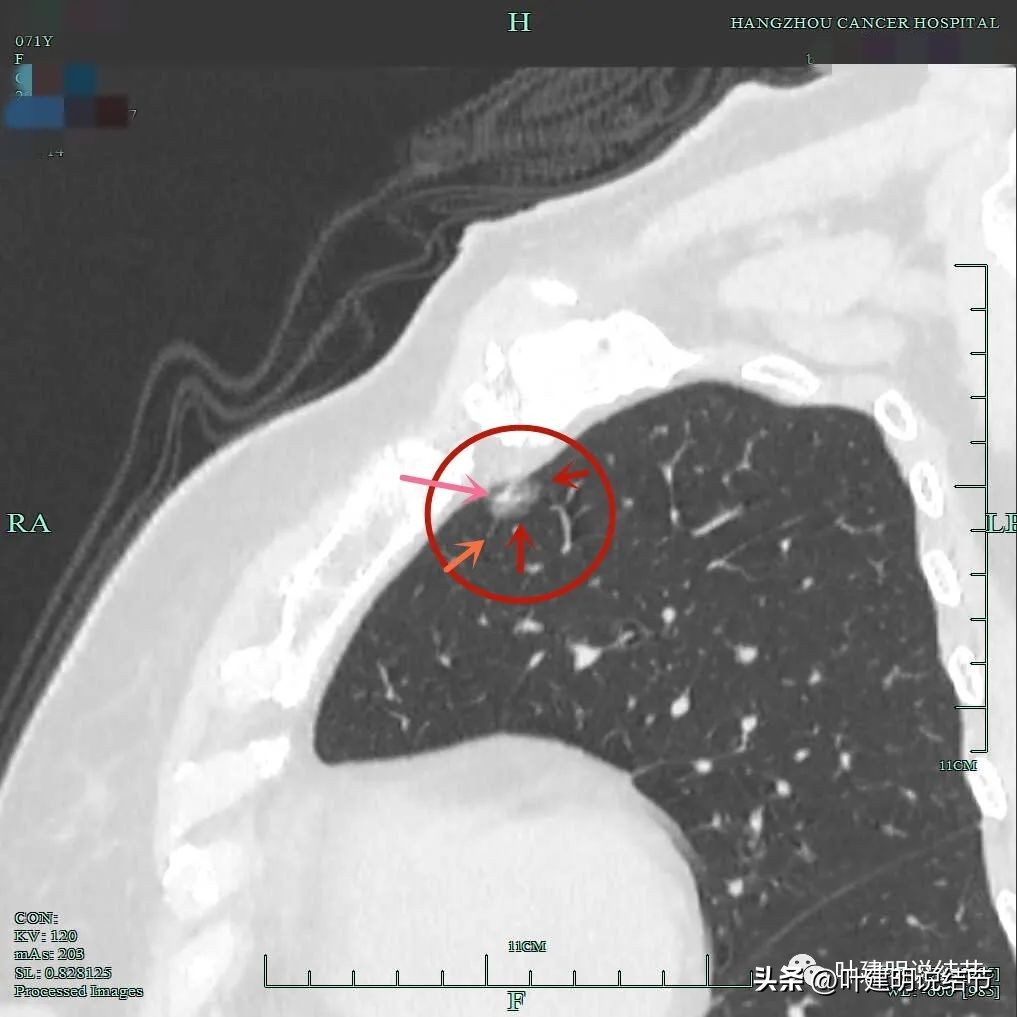

微血管征、毛刺征、混合磨玻璃密度、胸膜间隙征(黄色箭头)。

血管进入,混合密度,轮廓清。

左肺上叶两处病灶都要考虑是恶性的,其中主病灶混合磨玻璃密度,有微血管进入与穿行;有毛刺征;有胸膜间隙征;有表面不平与内部密度不均;有偏实性成分,应该是浸润性腺癌或微浸润性腺癌可能性大,位置好,能楔形切除,建议手术干预处理。左上次病灶小,但也是肿瘤范畴的,如果没有主病灶在,可随访,但主病灶要楔形切除,则可考虑一并切除。病理可能是不典型增生或原位癌可能性大些。